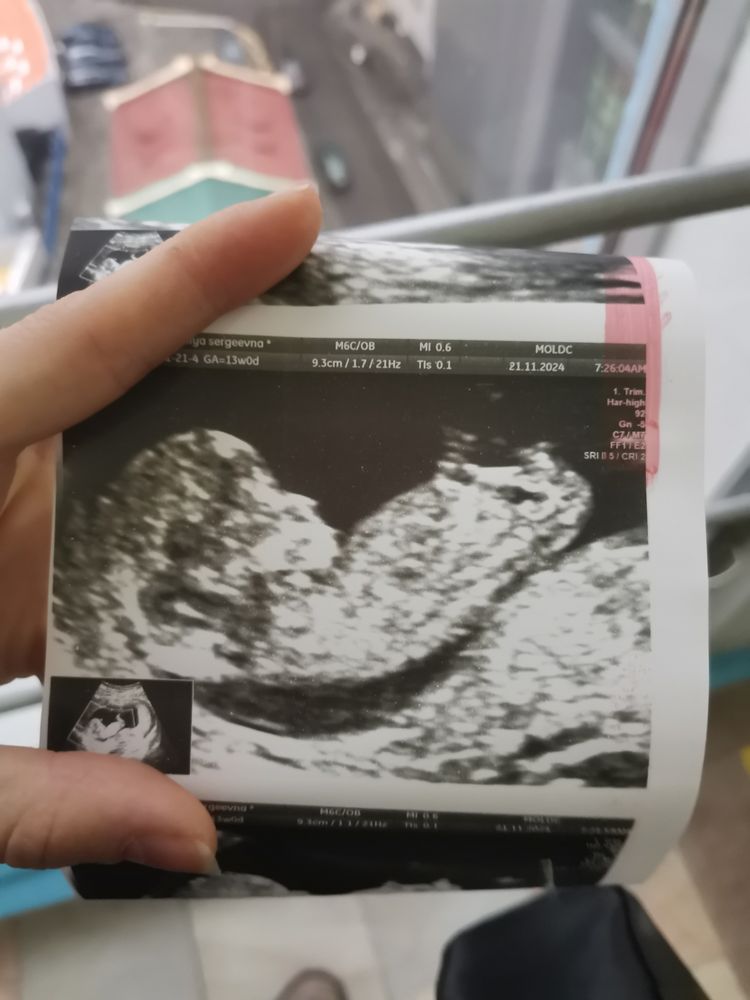

Пол малыша в 12 недель

Изображение

Ксения Синицина, плохое качество. Есть другие фото?

Ксения Синицина, смею предположить по половому бугорку, что это девочка. Но качество узи конечно не очень.

Ксения Синицина, мне на мальчика похоже, но с таким качеством фото нельзя утверждать. У девочек идёт параллельно позвоночнику, у мальчиков под углом. На вашем фото вроде под углом, но реально не понятно, может это вообще не бугорок 😄

Катэ, подчеркнула красным бугорок. Как раз параллельно спинке идет. Изображение

Евгения , это не бугорок, не девочка, я б на мальчика поставила, но правда видно плохо